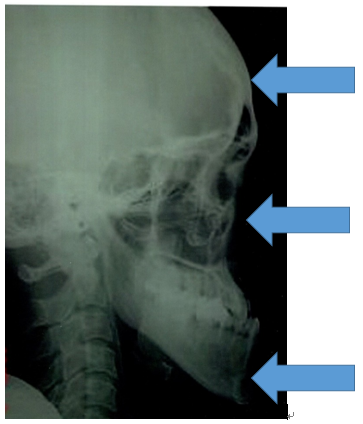

次に骨格で比べてみましょう。

同じ患者様の矯正治療終了後の骨格です。

不安定に見えていた咬み合わせが、反対咬合が改善されて安定して咬みあっていることが分かります。小学校低学年の治療であれば早期治療により反対咬合は容易に改善可能で、骨格の変化を考えてみても反対咬合は早期治療の効果が得られやすい症例と言えます。

骨格の変化は頭の上の方から

①頭蓋骨は形を楕円に変形させます。

②中顔面は凹みます。

③下顎骨は先端部分が厚くなり、三角形になります。このように、大人の強い咬合力で通常とは逆の咬み合わせで咬むために顔面頭蓋の骨の形を変化させるのです。

次に骨格で比べて診ましょう。

7歳 初診時 女子の受け口の骨格

7歳 治療終了時 女子の受け口の骨格です。

同じ人の1年後の骨格です。

小学校低学年の治療であれば、この変化は普通に起こる変化です。

骨格のことからも受け口は早期治療の効果が得られやすい症例です。